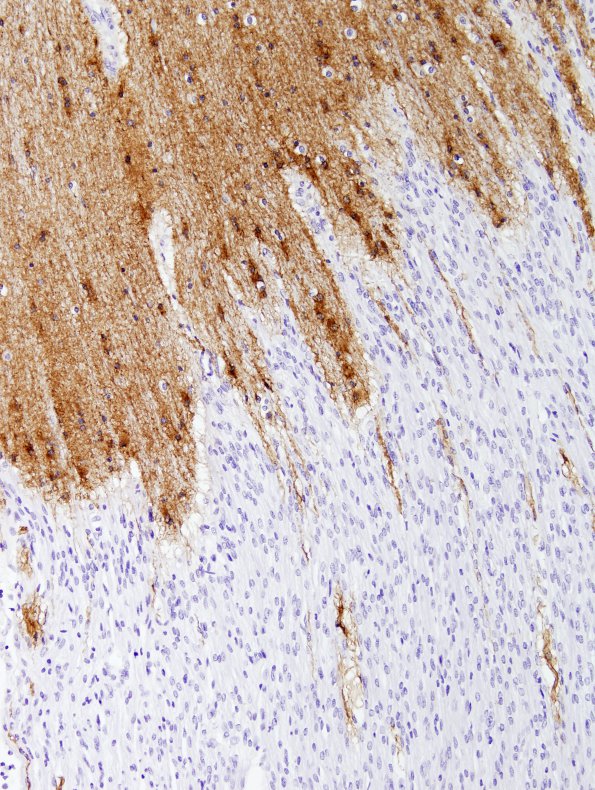

2C3 Brainstem, neonate, V Nerve (Case 2)  GFAP 2

The precise transition zone from CNS to PNS is shown (GFAP IHC)